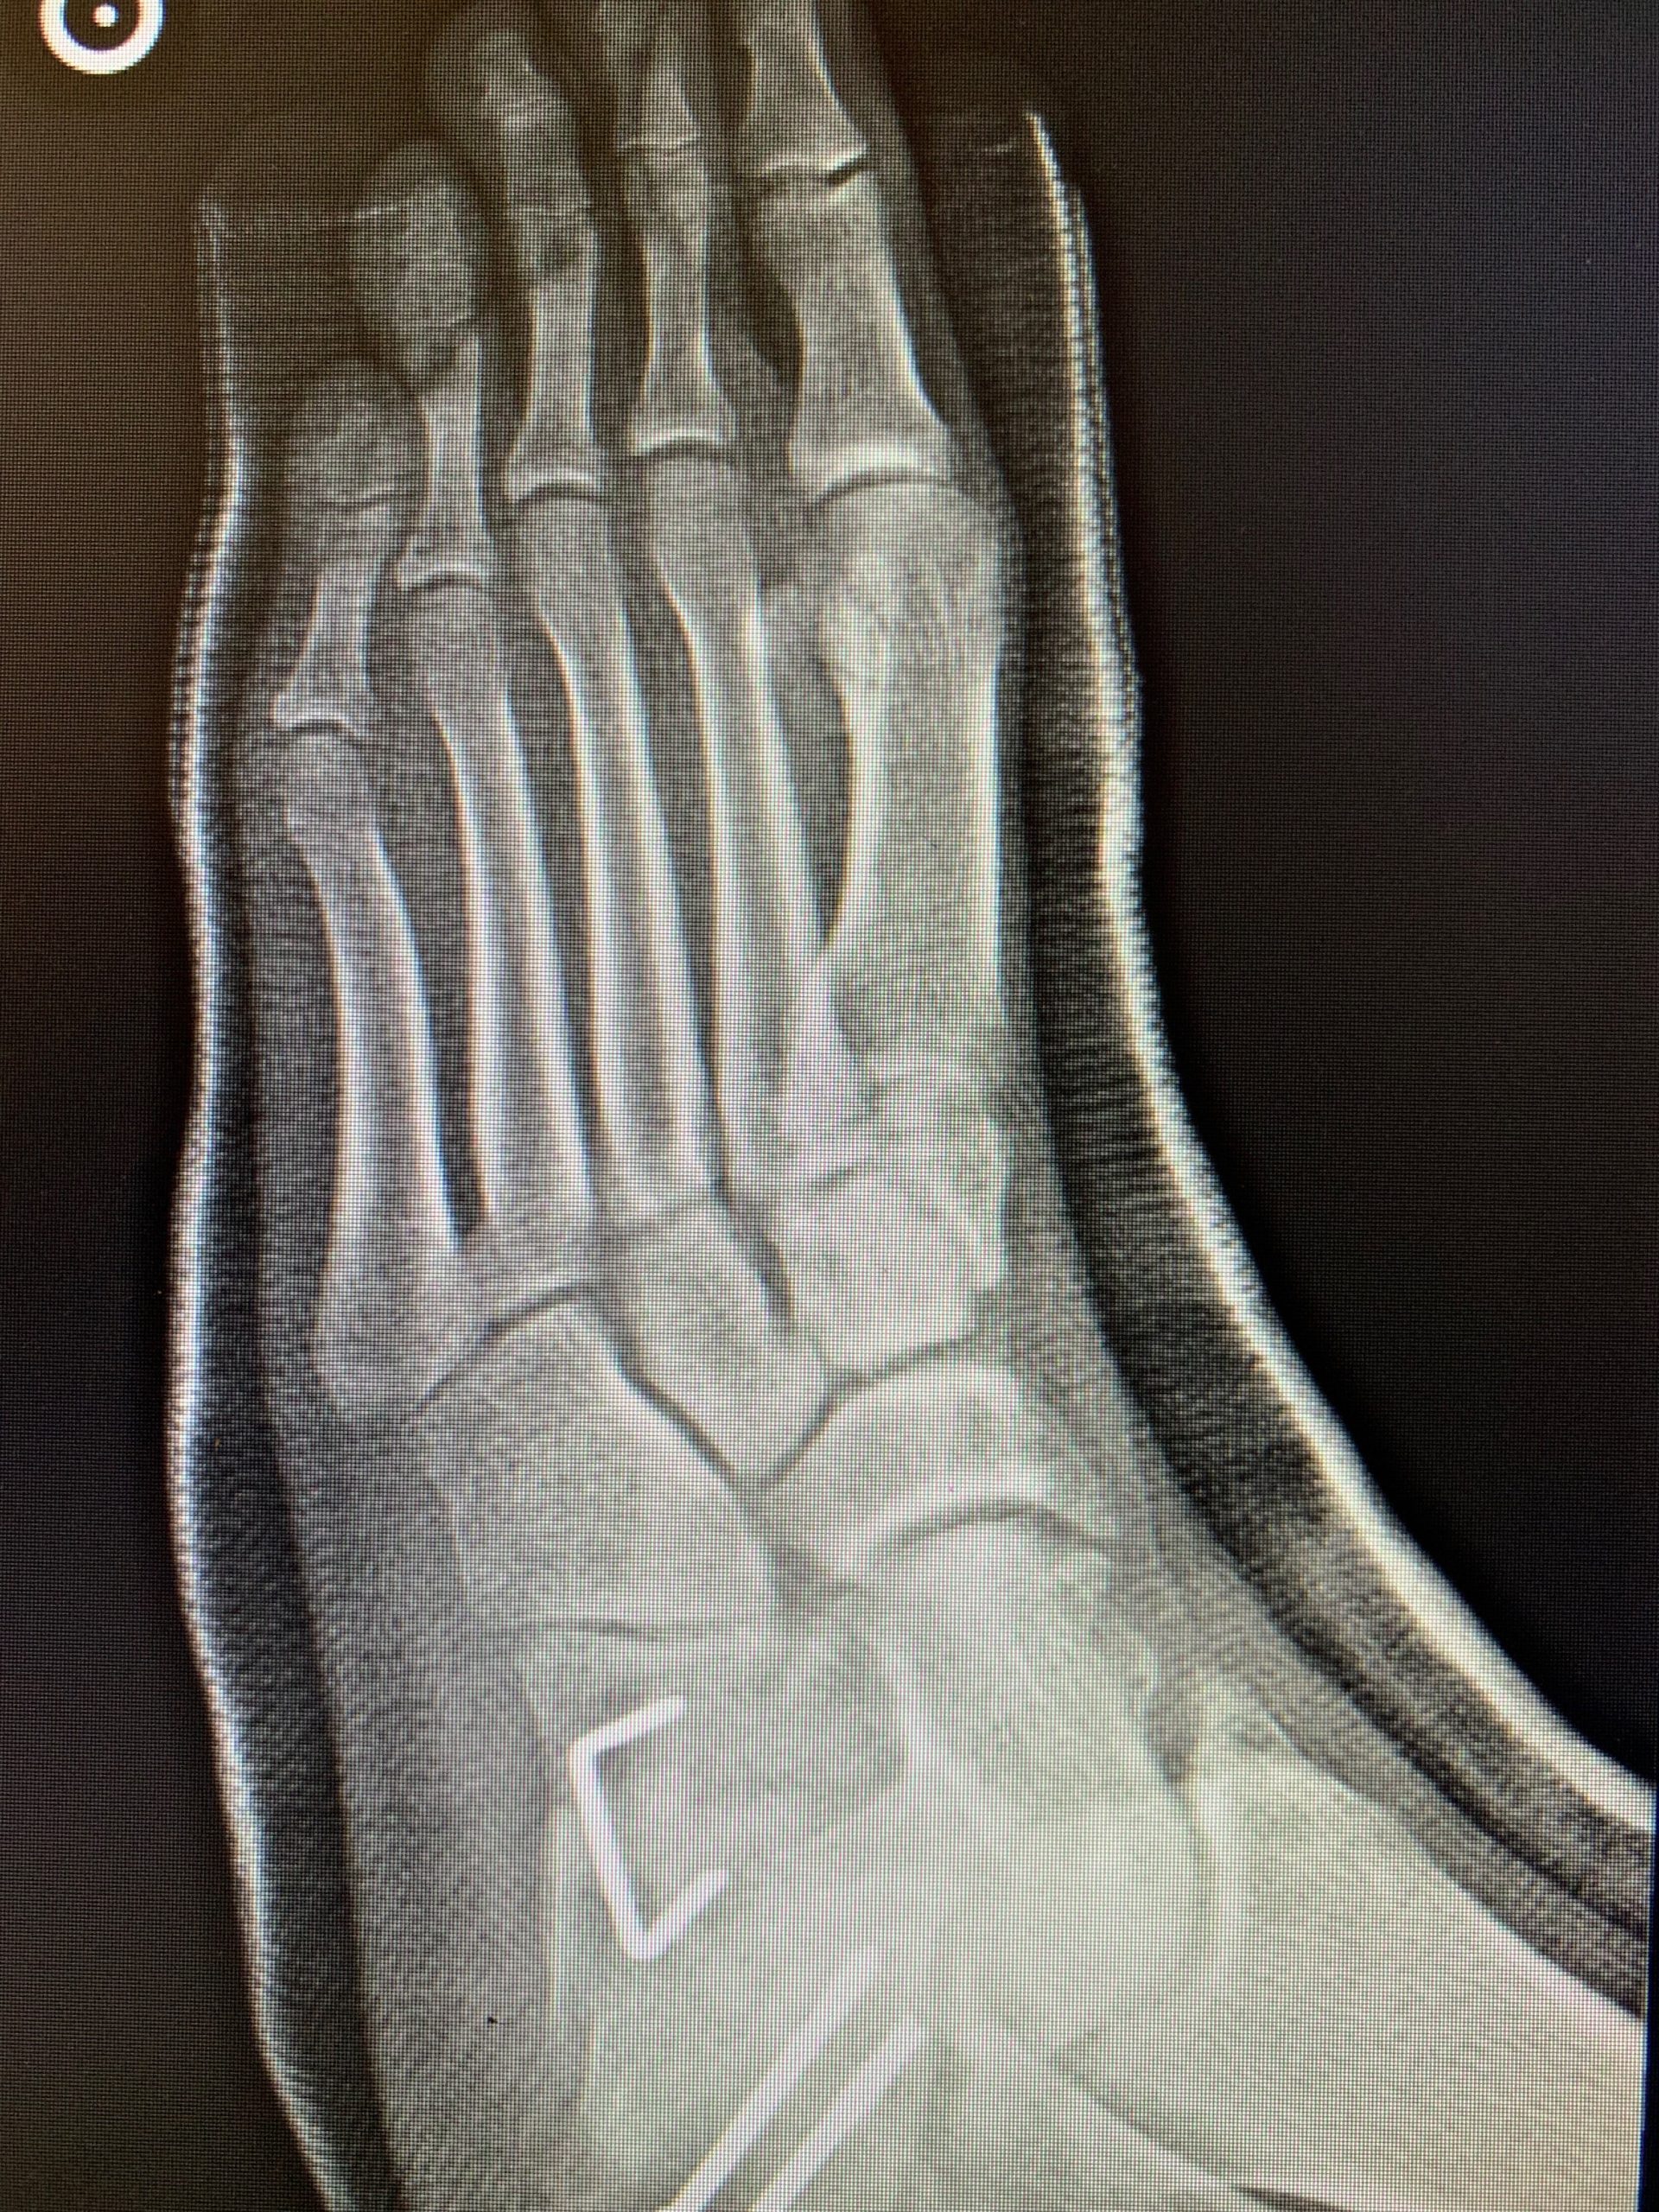

The foot is arguably the most complex part of the skeletal system with 33 joints, 26 bones, and more than 100 ligaments, tendons, and muscles.

What is foot deformities? In what diseases is it indicated? Primarily, it is the hallux valgus or bunion that consists of a deviation of the